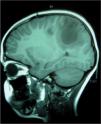

Se realiza resonancia magnética (RM) cerebral (figs. 1 y 2), en la que se visualizan hasta seis lesiones quísticas con cápsula hipointensa en secuencias potenciadas en T2, y con realce en anillo tras la administración de contraste, sugestivas de neurocisticercosis en fase coloidal.

Imagen de RM sagital que muestra las lesiones quísticas en sustancia blanca subcortical localizadas en lóbulos parietales, con fina cápsula hipointensa en T2, sugestivas de neurocisticercosis en fase coloidal. También se realiza espectroscopia de las lesiones, objetivándose gráfica patológica no tumoral.